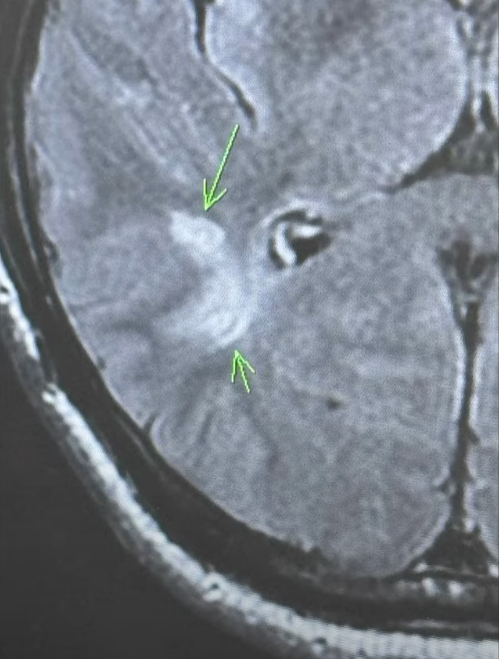

館長說,醫生建議目前先吃阿斯匹靈防血栓,等他下一趟中國行回來之後,就會去照MRI進一步確認狀況,現在的狀況是一部分血管不見了,但是血流自己找到了出路,所以目前對身體狀況,沒有造成影響,如果血流沒自己找到出路,他現在已經癱瘓了。

館長秀出X光片指出,腦部有一塊是白的、不見了,所以醫生安排檢查就是要找原因,並且盡快移除掉,畢竟現在沒影響,不代表以後沒影響。